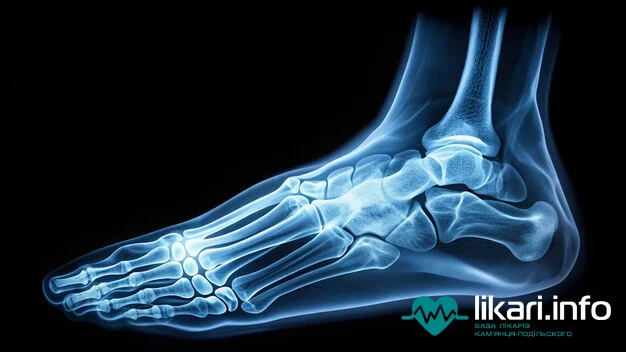

МРТ стопи — це один із найбільш сучасних і високоінформативних способів візуалізації м'яких тканин, кісток, сухожиль, зв'язок та дрібних суглобів стопи. Це дослідження є незамінним після травматичного пошкодження або для докладної діагностики ураженої ділянки безпосередньо перед плануванням хірургічного втручання. Проведення МРТ стопи можливе на апаратах потужністю 1,5 Тесла і вище.

MRI of the foot is one of the most modern and highly informative methods for visualizing the soft tissues, bones, tendons, ligaments, and small joints of the foot. This examination is essential following traumatic injury or for detailed pre-surgical diagnostics of the affected area. Foot MRI is typically performed on machines with a strength of 1.5 Tesla or higher.